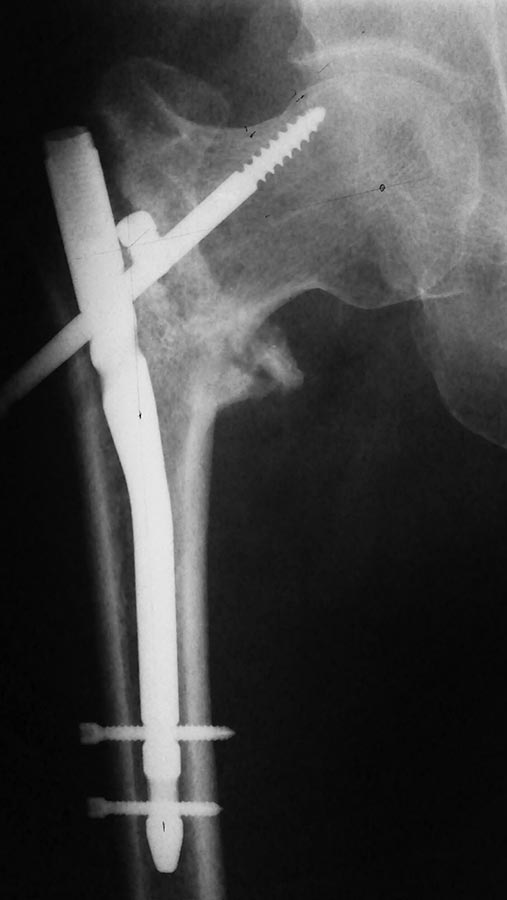

Травма, МОС PFN в апреле 2015 В июне миграция шеечного винта, удаление его. На данный момент в течение недели усилились боли, ходит с костылём с частичной нагрузкой на конечность. Имеем вот такой снимок. Консультирован дважды в областной, рекомендовано в 1 сучае лечиться далее консервативно, а другом протезирование сустава. Собственные мысли: Удаление МК, ремос в нормальном вальгусном положении шейки. Этим же стержнем? По документам это Beznoska. Можно раздобыть установочный инструмент. DHS видится неплохим вариантом, но его нет в наличии. Протезирование имеется, но не хочется -норм.сустав. прошу совета.

Это хороший аксиальный снимок. Хотя ситуация понятна, фас желательно тоже увидеть.

Мы бы сделали вальгизирующую межвертельную остеотомию с фиксацией внутрикостным гвоздем. Желательно спланировать положение имплантата в интактных участках головки. Возможно, стоит подумать об аугментации ее, т.е. заполнении дефектоа от прежних шеечных винтов чем-то.

Доброго времени суток! Анамнез без особенностей- мужчина 45-49 лет, не алкаш, рработяга. В п\о периоде как уже писал миграция шеечного винта, удаление его. Сначала вроде начал ходить с опорой, потом усилился б\с, ходит с костылём. Вторая проекция.

Для шеечного компанента как минимум - клинковая пластина или заполнение полости... цементом, если аутокость. то длительная иммобилизация в кокситной повязке (8-12 недель). Вальгизация - обязательна.

Винт-заглушка в линии перелома. Как он туда попал? Не поэтому-ли прямую проекцию не хотели показывать)))

Надо удалять. Похоже, остается только протезирование, т.к. шейка "пустая", по снимку видно, что винт прорезался и сместился краниально, на аксиале тоже видно. Поэтому Гамма не пойдет, пластина на спонгиозных винтах тоже. Можно конечно цемента напихать, потренироваться... А стоит? Думаю протез лучший вариант.